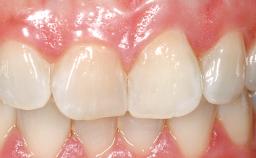

Late Flapless Placement of an Implant in a Maxillary Left Central Incisor Site

Prosthesis Type FDP

SAC Level Advanced

Defining Characteristics One missing tooth to be replaced by an implant-borne crown

Loading Protocol Conventional or early

Retention Cemented, with prosthesis margin < 3mm submucosal Cemented, with prosthesis margin < 3mm submucosal

Provisional Implant-Supported Prosthesis Prosthodontic margin < 3 mm apical to mucosal margin Prosthodontic margin < 3 mm apical to mucosal margin